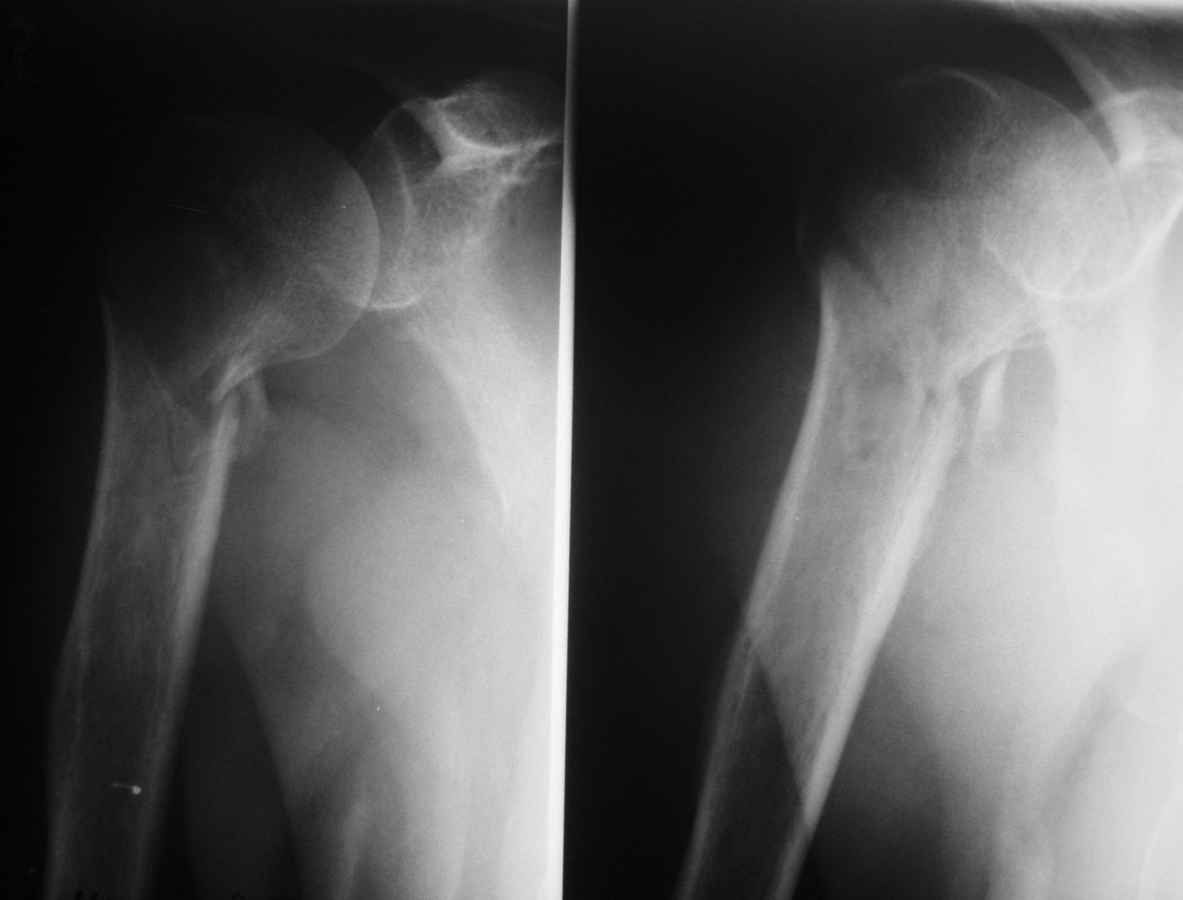

Перелом хирургической шейки плеча

Пациент 55 лет. травма 7.07.09г (первая Р-грамма). Лечился консервативно, надолго выпадал из под наблюдения леч. врача. Последний снимок от 7.08.09 г. Как видно на Р-грамме, стояние отломков неудовлетворительное, клинически выраженная патологическая подвижность. Соп. дз: сахарный диабет 1 типа, средней тяжести. Выскажите Ваше мнение о дальнейше тактике лечения данного пациента.